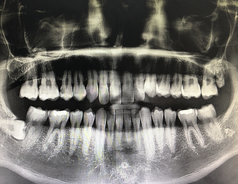

구강암 초기증상 원인 생존율 치료방법 등 구강암에 대한 정보를 알아보도록 하겠습니다.

구강암(Oral cancer)은 구강에서 발생하는 악성 종양으로, 구강암의 원인에는 흡연, 알코올 사용, 악성발암 세포, 인자, 상한 상태, 빈맥 등이 있습니다. 구강암의 증상으로는 입안의 통증, 피부 색상 변화, 혈관의 팽창, 입술의 변형, 입안의 표피 바람 등이 있습니다. 이러한 증상이 발생할 경우 빠른 진단이 필요하며, 의사와의 상담과 적절한 치료를 통해 예방할 수 있습니다.

구강암은 입술, 혀, 입술 내부, 치은, 무치성 부위 등에서 발생할 수 있는 암 종류 중 하나입니다. 초기에는 통증이나 불편감이 느껴지지 않아 진단이 어렵기 때문에, 정기적인 구강 검진이 중요합니다. 그러나, 다음과 같은 초기증상이 발견된다면 구강암 의심이 있으므로, 신속하게 의료진과 상담해야 합니다.